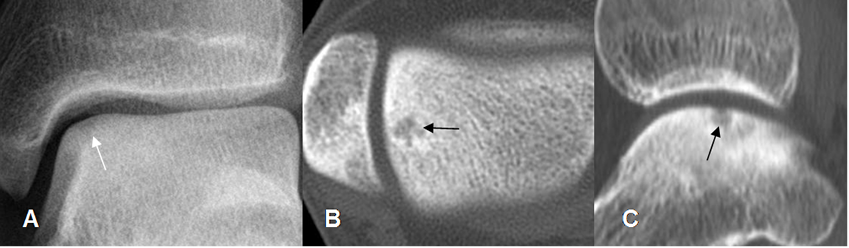

Fig 41. Lesión osteocondral estado IV.

A: TAC axial, B: TAC reconstrucción coronal y C: TAC reconstrucción sagital. Lesión osteocondral en la parte superoexterna del talo, con gran fragmento óseo desprendido.